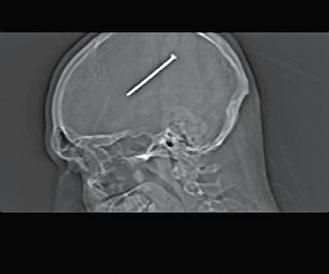

这张X光片中可以清楚看见打进芝加哥男子奥图洛脑子里的长钉。

去年1月,住在芝加哥郊区的美国男子奥图洛在车库里工作时,打钉枪意外射出一根钉子。他以为钉子从他的头旁边飞过去,可是遍寻不着。后来因为剧烈头疼就医,才发现这根8.25厘米长的钉子居然卡在他的脑部。

经X光检查,发现他头上有根钉子,而且只差一点点就伤到控制运动机能的部分。医生立刻动手术,花了4个小时把钉子取出来,并用网子和钛金属板替代他的部分头壳。